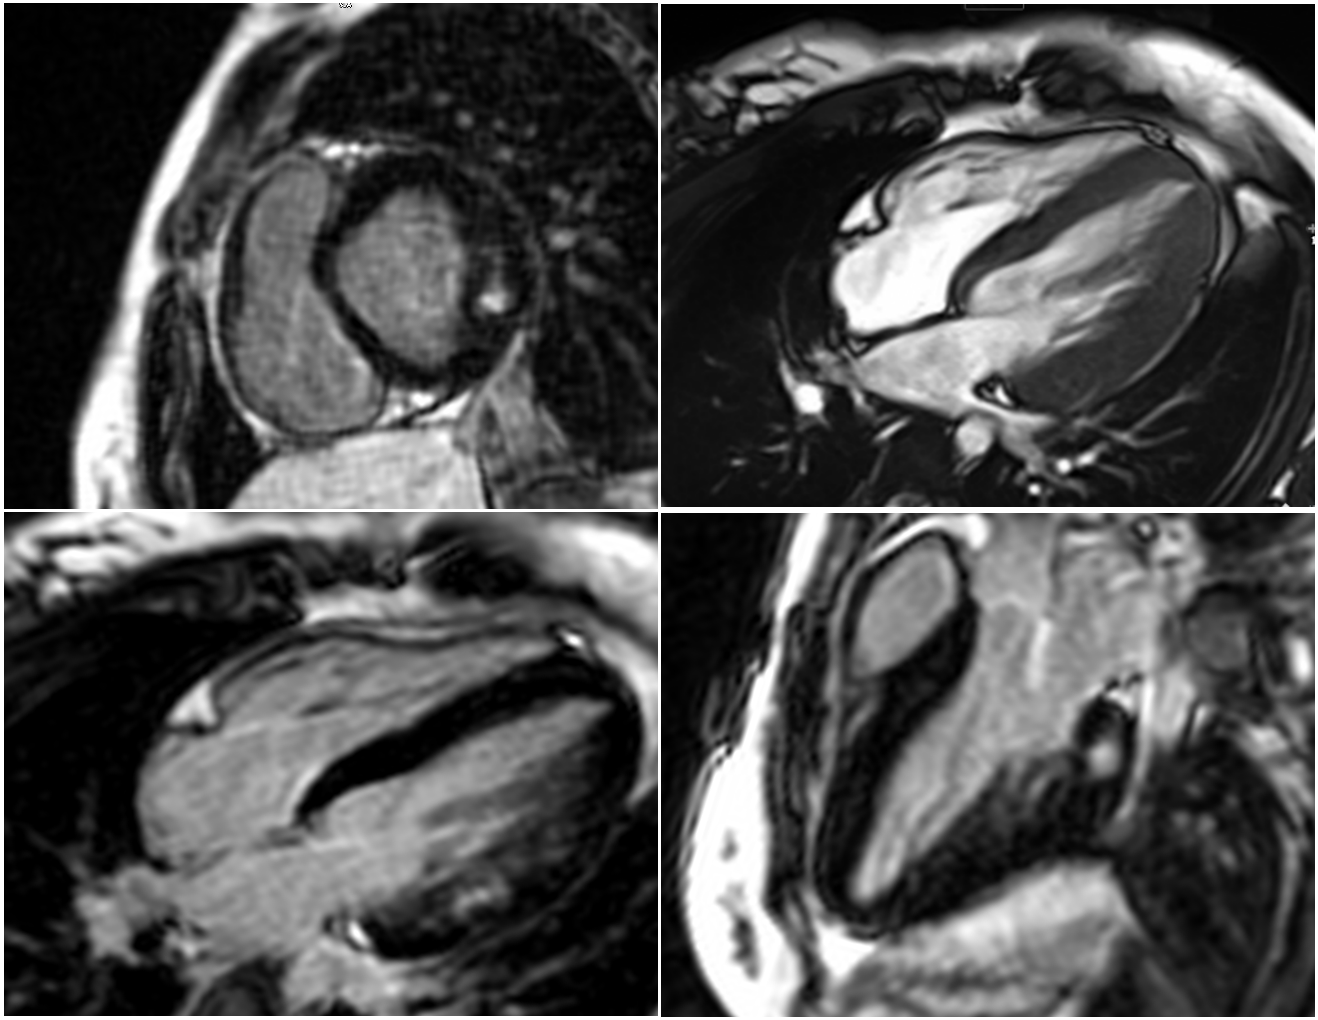

Right: T2 mapping; Left: T1 mapping in a four-chamber view, both showing markedly elevated T2 and T1 values in the lateral wall of the left ventricle with relative sparing of the basal–mid interventricular septum.